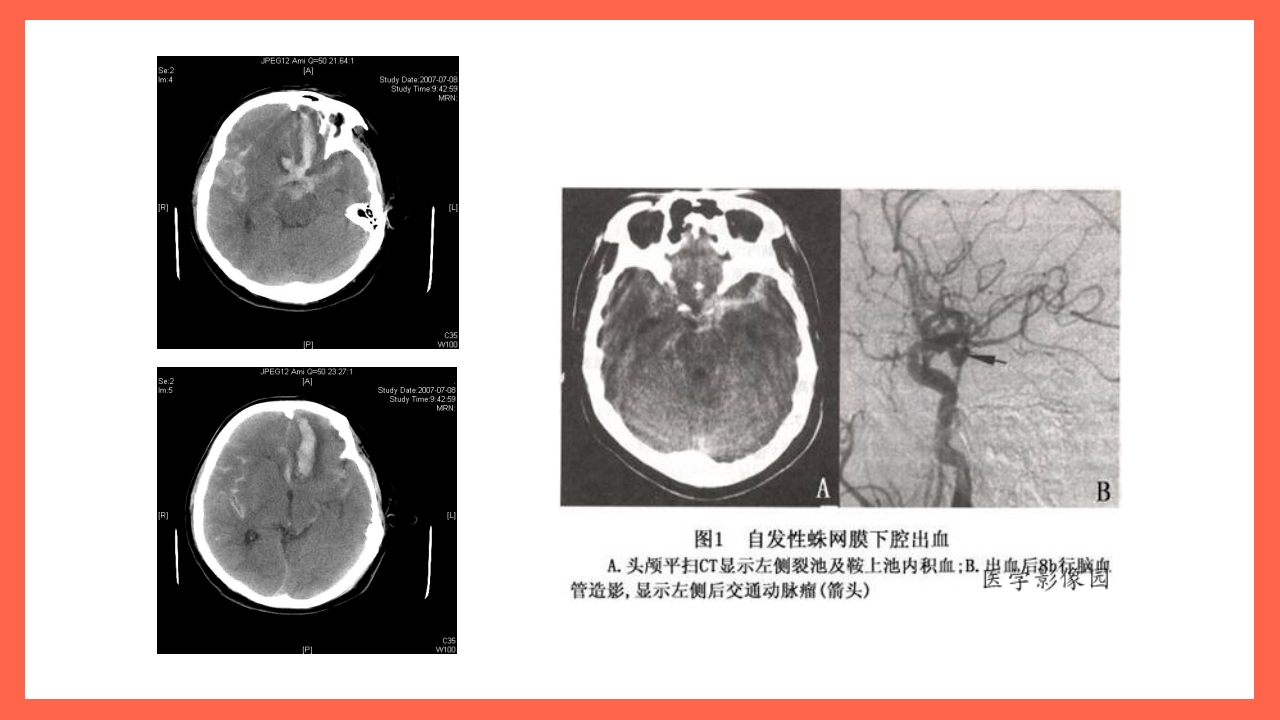

蛛网膜下腔出血的护理 关/注/通/路 用/心/呵/护 讲述人:xxx 日期:20××.××.×× 概念 颅内血管破裂后血液流入 蛛网膜下腔时称为蛛网膜 下腔出血(SAH)。 概念 (一) 原发性SAH (三) 外伤性SAH 蛛网膜下 腔出血( SAH) (二) 继发性SAH (四) 自发性SAH 病因 、颅内肿瘤、 血液病、妊娠并发症、结蒂组织病、 抗凝治疗的并发症等 蛛出 血病 网 理 膜 生理 下 腔 血管活性物质 血细胞破坏 脑血管痉挛 血液 蛛网膜下腔 沉积脑池 部分脑池 刺激血管 脑积水 临床表现 起病骤急 年龄 脑膜刺激征 SAH的临 床表现 头痛与呕吐 意识障碍和 精神症状 并发症 再出血:是 SAH致命的并发症。出血后一 个月内再出血 01 危险性最大,二周内再发率占再发病例的54%-80%,再...